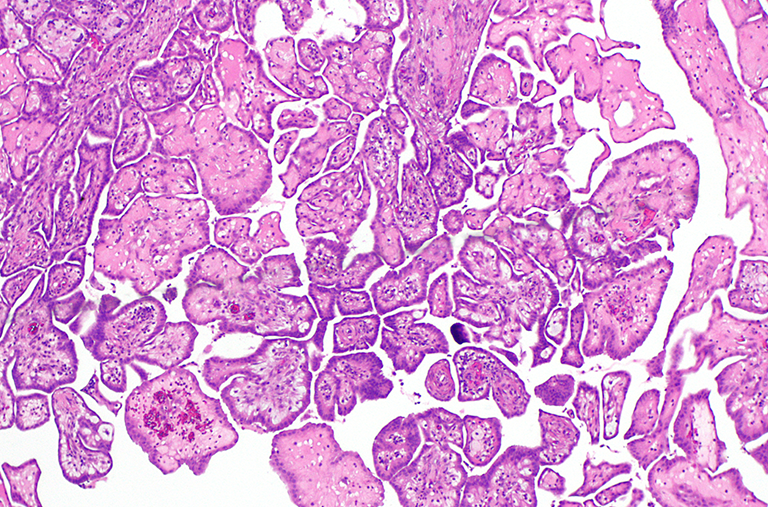

While a Partner at his former firm, Michael J. Goldberg helped earn one of the highest annual medical malpractice recoveries in Winnebago County involving an infant for a 3-month-old child who died as a result of medical malpractice. The facts included a baby boy who suffered from Hirschsprung’s Disease, which went undetected and misdiagnosed for three months.